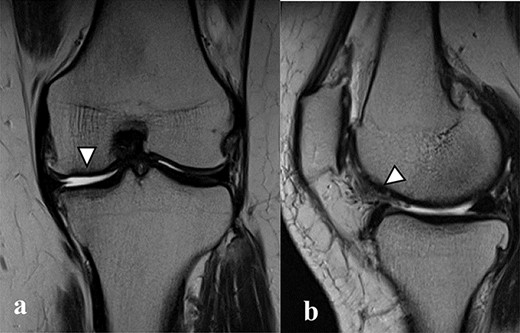

There were cartilage defects (arrowhead) in the medial femoral condyle and trochlea of the left knee (a, b).

Articular cartilage injury was shown in the medial femoral condyle (arrowhead) (2.5 × 3.5 cm; Outerbridge classification, Grade III) and trochlea (arrowhead) (1.3 × 1.7 cm; Outerbridge classification, Grade III) (a, b).

A 42-year-old female (BMI, 27.4 kg/m2) presented with 2 years of left knee medial joint pain. Active range of motion (ROM) in the left knee was from 0 to 140 degrees with no extension lag. Preoperative Tegner scores, Lysholm scores and Knee Injury and Osteoarthritis Outcome (KOOS) scores are shown in Table 1. Preoperative radiographs of the left knee joint showed mild medial osteoarthritis (OA) of the knee and hip–knee–ankle (HKA) angle of 1.5-degree varus. 1.5-Tesla MRI was performed on unit (Toshiba, Kawasaki, Japan) was used with an extremity surface coil. Proton density images were obtained using the fast spin-echo technique. A modified magnetic resonance observation of cartilage repair tissue (MOCART) system was used for the quantitative evaluation of MRI findings of the cartilage injury [15–17]. MRI showed cartilage injury of the medial femoral condyle (MFC) and trochlea of the left knee (Fig. 1).

MRI showed cartilage injury of the medial femoral condyle (arrowhead).